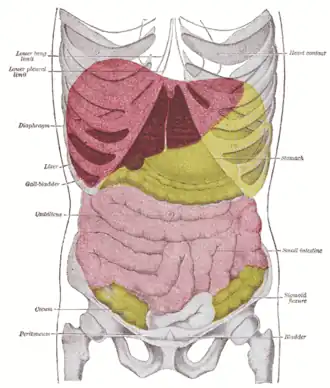

Abdominal trauma is an injury to the abdomen. Signs and symptoms include abdominal pain, tenderness, rigidity, and bruising of the external abdomen. Complications may include blood loss and infection.

Diagnosis may involve ultrasonography, computed tomography, and peritoneal lavage, and treatment may involve surgery.[1] It is divided into two types blunt or penetrating and may involve damage to the abdominal organs.[2] Injury to the lower chest may cause splenic or liver injuries.[3]

One or more of the intra-abdominal organs may be injured in abdominal trauma. The characteristics of the injury are determined in part by which organ or organs are injured.